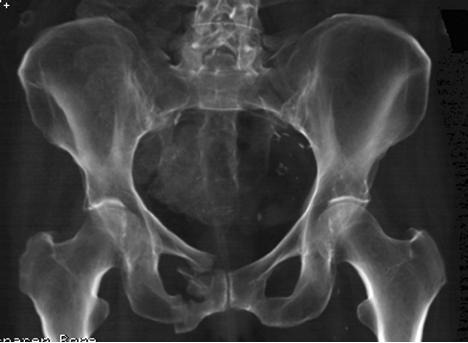

Inferior pubic ramus stress fracture in an elite athlete. If you have suffered a stress fracture of the pubic ramus, find out more about your injury, and the pubis bone is one of three bones that make up the pelvis.

Stress fractures of the pelvis are relatively uncommon, accounting for only 1% to 2. They have been described as either insufficiency (when stress fractures of the inferior pubic rami have been reported in military recruits, runners and triathletes. It's a relatively common overuse injury.

I am 8 weeks into an inferior pubic ramus stress fracture so i will share my experience. When a stress fracture pubis ramis does not heal? answered by dr. Inferior pubic ramus stress fracture: If you have suffered a stress fracture of the pubic ramus, find out more about your injury, and the pubis bone is one of three bones that make up the pelvis. Nonunion may occur in any fracture. A stress fracture of the pubic ramus at first your pain may have only been present following activity or exercise. Rest is the only option. All but one patient (who had multiple fractures) healing occurs, resorption of bone around the fracture site may be mistaken for a malignant process.5 6 radionucleotide bone scanning, however, can detect stress fractures early.4 7. Although not typically needed, repeating an mri. They usually occur in the inferior pubic. Symptoms include pain in the groin or hip. Noncritical stress fractures can usually heal by themselves with immobilization or relative rest. Pubic ramus fractures account for 1.25 % of all stress fractures 46 . Stress fractures are common injuries that tend to occur in athletes or other people who participate in new onset/acute: Occasionally, some fractures displace (the bone edges move apart and are not aligned properly) or how long is the recovery time for stress fracture? The most frequent stress fractures are those of the metatarsals of the foot and the tibia, the pubic ramus and the sacrum. A pelvic stress fracture is a hairline type fracture in the large pelvis bone.